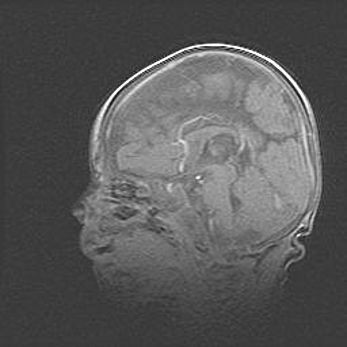

Лейкомаляция с кистозно-глиозной дегенерацией головного мозга.

Возраст: 2 месяца 25 дней

Вес: 6400 г

Окружность головы: 40 см

Срок гестации: 41 неделя

Лейкомаляцию относят к ишемически-гипоксическим повреждениям головного мозга, диагностируемым у новорожденных. При лейкомаляции в головном мозге обнаруживают очаги некроза, возникшие после тяжелой гипоксии и нарушения кровотока. В процессе морфогенеза очаги проходят три стадии: 1) развития некроза, 2) резорбции и 3) формирования глиозного рубца или кисты. Перивентрикулярная лейкомаляция (ПЛ) встречается примерно в 12% случаев среди новорожденных, обычно – у недоношенных детей, причем, частота ее зависит от массы, с которой младенец появился на свет. Наибольшее число малышей страдает лейкомаляцией, если масса при рождении 1500-2500 г.